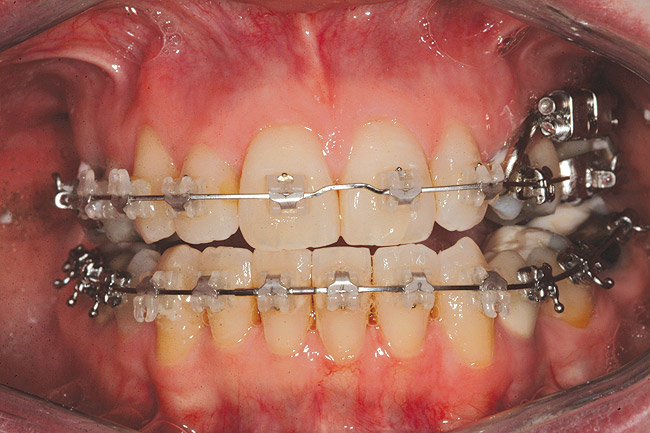

Fig 12 (and Fig 13). Incisors were too upright and had severe incisal wear. He was concerned about esthetics of the worn teeth and his insufficient lip support. Progress photo and panorex 9 months after corticotomies were performed on Nos. 6 through 11. Previous extraction sites were reopened orthodontically to improve function and fill lip support. Incisal edges were restored provisionally with composite resin. Note that despite the creation of adequate spaces to replace missing teeth, there is inadequate room for placement of dental implants because of severe tipping of all the anterior teeth. Osteotomy SFOT may have been a better choice because it would have allowed needed alveoloskeletal correction (without excessive tipping) instead of the primarily dentoalveolar correction common in corticotomy SFOT. Restorative dentist: Brad Jones, DDS.

Fig 13 (and Fig 12). Incisors were too upright and had severe incisal wear. He was concerned about esthetics of the worn teeth and his insufficient lip support. Progress photo and panorex 9 months after corticotomies were performed on Nos. 6 through 11.